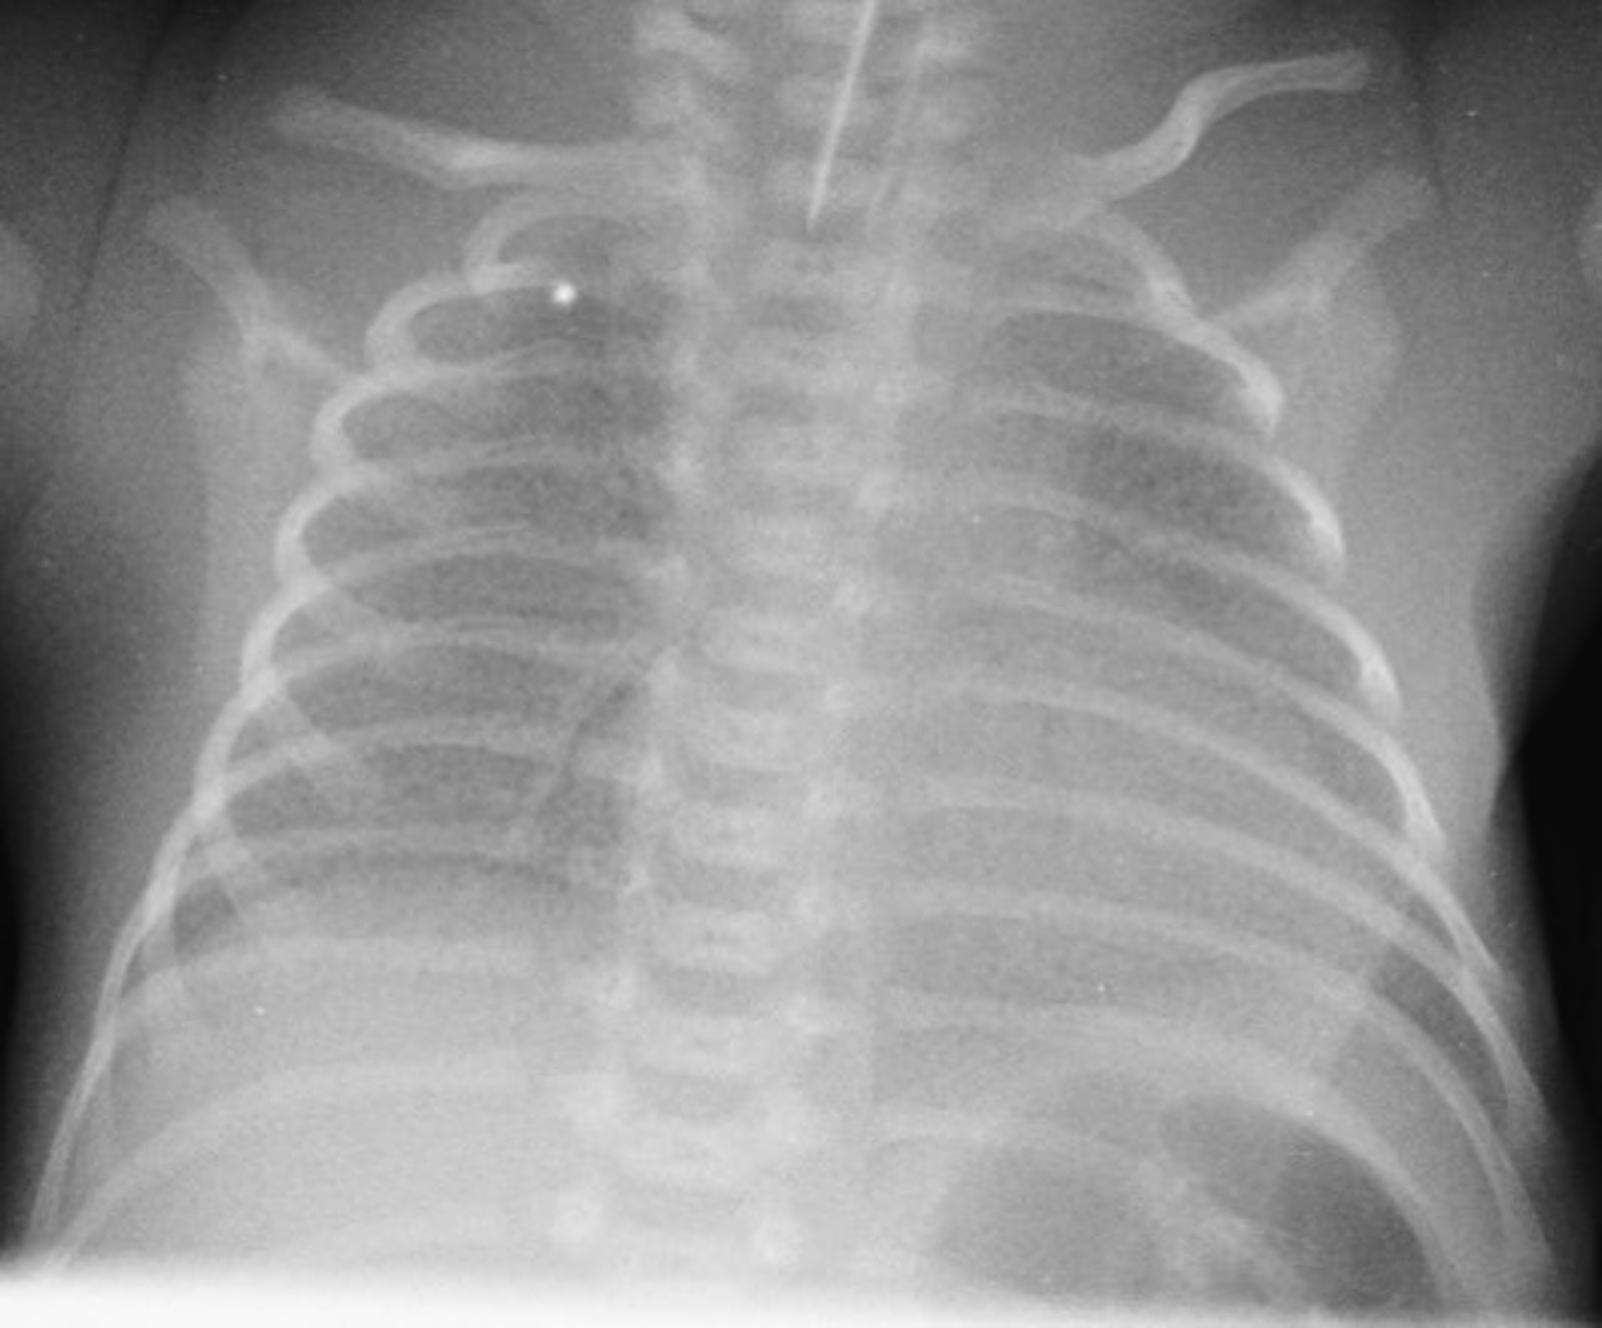

A 7-day-old female patient is brought to your emergency department by ambulance for difficulty breathing. She was born via spontaneous vaginal delivery at 37 weeks gestation and had an uncomplicated hospital stay and was discharged at the end of day 2 post-delivery. Over the past day she began developing a cough and fever to 101°F, decreased feeding, and “fast breathing”. Her vital signs are significant for a heart rate of 180 beats per minute, a rectal temperature of 102.1°F, a blood pressure of 78/44mmHg, a respiratory rate of 70 breaths per minute, and an oxygen saturation of 85% on room air. On physical examination she appears lethargic. She is tachypneic with retractions bilaterally, slightly dry mucous membranes, and coarse breath sounds over the right lower lobe. Despite supplemental oxygen via nasal cannula at 6 liters per minute, her oxygen saturation only increases to 91%. Her chest radiograph (CXR) is seen in Figure 2.1.

FIGURE 2.1. AP view of the chest demonstrates bilateral diffuse pulmonary air space opacification.

streptococcus is the most common causative organism. Late onset pneumonia usually occurs after discharge; or, in the hospital, it is commonly acquired from the neonatal unit or is associated with mechanical ventilation. Signs of neonatal pneumonia may mimic those of TTN and respiratory distress syndrome (RDS). Nonrespiratory signs include temperature instability, apnea, poor feeding, and lethargy. CXR can have protean imaging manifestations with radiographic findings potentially mimicking those seen in RDS, transient tachypnea of the newborn, and meconium aspiration. Isolated focal consolidation is rare with bilateral airspace disease most common, as seen in Figure 2.1. The presence of a pleural effusion can be a helpful distinguishing feature, being described in up to two-thirds of cases, such as in Figure 2.4.

FIGURE 2.4. Neonatal pneumonia in a neonate with a small right pleural effusion (arrow) and diffuse left and right lower lobe hazy pulmonary opacification.